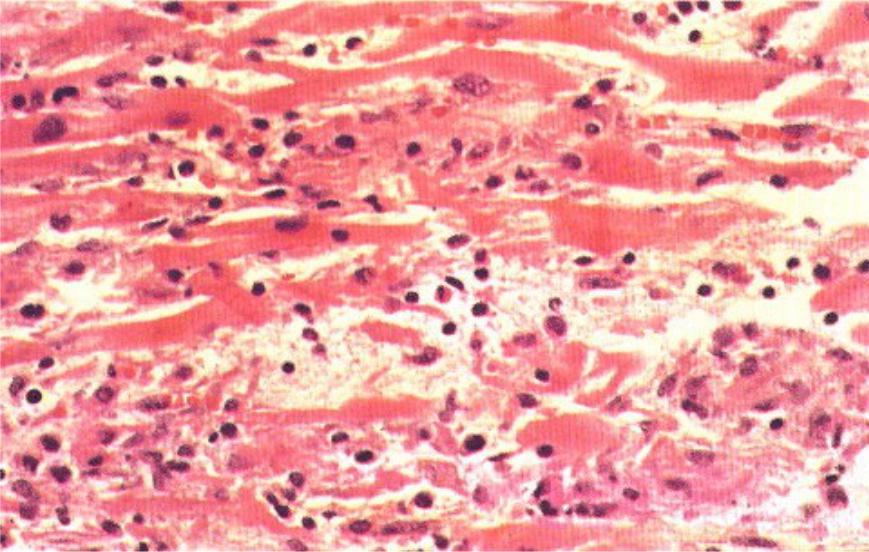

Межуточный миокардит: гистологические исследования

Раздел: Идеи и советы